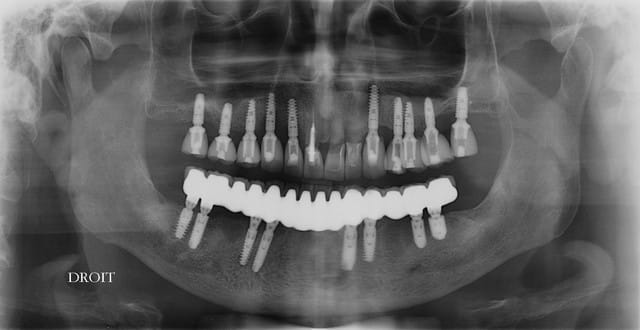

Sinon pour les cas de bridge complet sur 8 implants j'aime bien faire 4 bridges 3 dents sur deux implants quand on le peux. Pas possible par contre quand on rajoute de la fausse gencive comme c'est le cas ici.

Implants bien parallèles, classe!

ouarf, mdr, l'implant en 47 est lingualé et tous les autres à partir du secteur antérieur partent sur la droite...comme pour tous les droitiers....

Professeur Pluton, tu devrais être plus cool avec les confrère moins doué que toi, en fait je me suis laissé guidé guidé par l'os et l'axe de la future prothèse mais bien sur, à main levée, puisque je n'ai pas les compétence pou me servir d'un outil geek.

Il me semble tout à fait normal que 47 n'ai pas la même inclinaison que 46 dans le sens vestibulo lingual...

A ce sujet, plutôt que de looker l'axe de 47, jette un œil sur 26 .... il ne s'agit pas de montrer que je suis le meilleur, mais que des techniques simples et bien raisonnées permettent d'obtenir des résultats corrects et reproductible, et ce par n'importe quel dentiste consciencieux.

pour 26 (comme pour les 17 autres implants de ce cas) flapless intégral (même pas de puch), foret initial directement à travers la gencive) et uniquement des éponges de Gelatemp là où c'était nécessaire.

Donc coût très réduit, ce qui pourrait permettre de réduire au maximum le devis des implants....mais en réalité ça me permet surtout d'augmenter ma marge et de travailler moins pour le même résultat en fin d'année...:-))